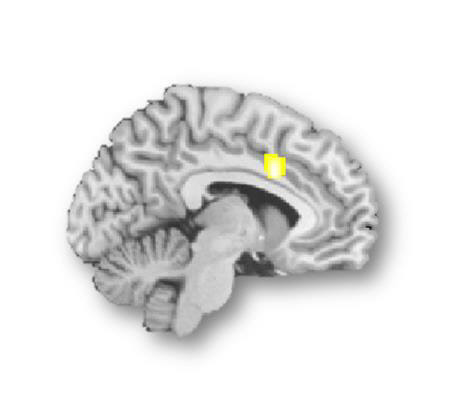

특히 뇌기능 MRI 영상에서는 갈등의 탐지와 조절에 관련된 뇌 속 '배외측전전두피질'과 '전대상피질'에서 상대적으로 저하된 뇌활성화가 관측됐다.

뇌기능 MRI 영상에서 갈등의 탐지와 조절에 관련된 뇌 속 '배외측전전두피질'과 '전대상피질'에서 상대적으로 저하된 뇌활성화가 관측된 모습. [연구팀 제공]